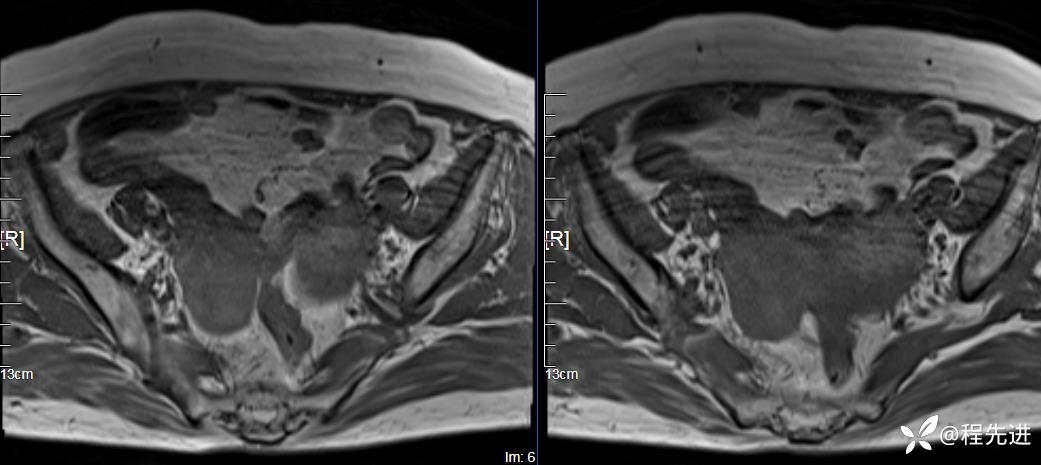

T1: